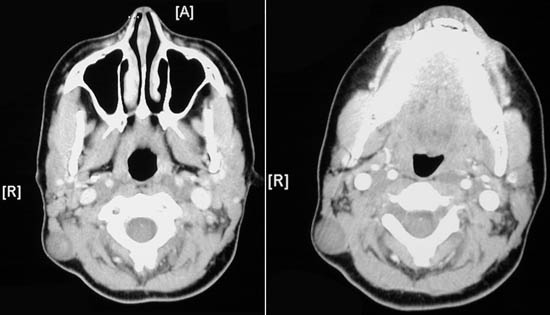

| The subcutaneous masses seen above with a head CT scan at the level of the maxilla and at the level of the jaw are neurofibromas in a patient with neurofibromatosis type I (von Recklinghausen disease). Another neurofibroma appears in the thigh region as seen with MRI scan below (axial T1 on the left; coronal STIR on the right). NF1 is an autosomal dominant condition. Half of cases result from new mutations in the NF-1 gene on chromosome 17 which encodes for a protein that is a negative regulator of the ras oncoprotein. Overactivity of ras leads to neoplasia, specifically development of neurofibromas in nerves and dermis anywhere in the body. |